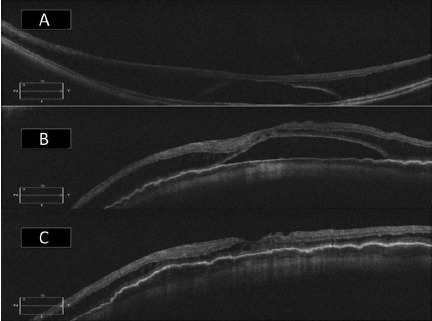

3.png

图 3 A 为后巩膜葡萄肿黄斑脱离无黄斑裂孔患者术前 OCT;B 为同一只眼黄斑扣带术后 1 周 OCT ,黄斑脱离部分恢复;C 为同一只眼术后 6 周 OCT 显示黄斑脱离完全复位(扣带组)

4.png

图 4 A 为后巩膜葡萄肿黄斑劈裂且无黄斑裂孔患者眼术前 OCT;B 为同一只眼术后 8 周 OCT ,黄斑劈裂完全恢复,黄斑、脉络膜以及巩膜扣带处变平(扣带组)